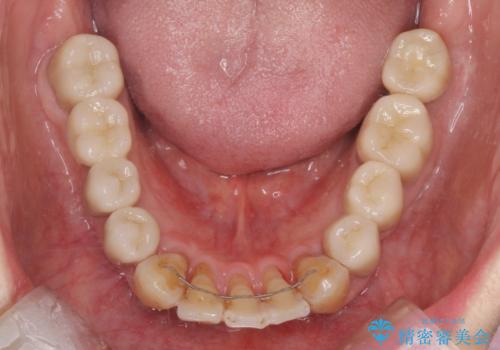

インプラント治療に加え、歯周病に対しての再生治療や歯周ポケットの除去を行う歯周外科、矯正治療、と必要な治療は多岐に渡りましたが、最終的に安定した噛み合わせを得られたとともに、清掃のしやすい口腔内環境を確立できました。